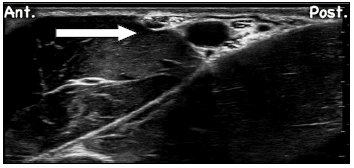

Observe a imagem relacionada ao bloqueio do plexo braquial ao nível axilar:

O nervo destacado pela seta é o: